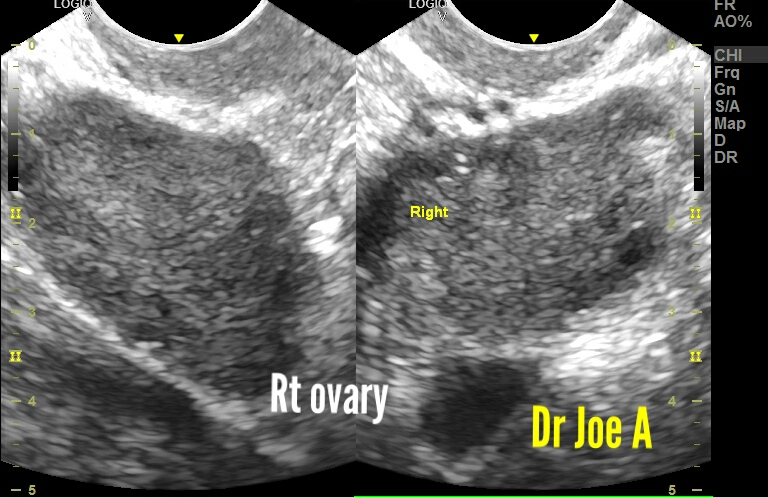

What could be wrong with these ovaries?

Patient of menstrual disorders.

Transabdominal ultrasound showed slightly enlarged ovaries.

TVS ultrasound scan showed these findings:

Ovarian enlargement obvious.

But those follicles are not normal either.

The ovaries are definitely enlarged at 16 and 18 cc. Anything more than 10 cc is definitely in favor of polycystic ovaries.

Peripheral follicles and small follicles are also supportive of PCOD.

Final diagnosis:

PCOD in young woman 👧.